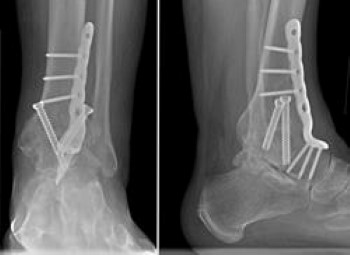

Fusion. Fusion of the affected joints is the most common type of surgery performed for RA. Fusion takes the two bones that form a joint and fuses them together to make one bone.

During the surgery, the surgeon exposes the joints are removes the remaining cartilage. The two bones are then held together with screws or a combination of screws and plates. This prevents the bones from moving. By limiting motion, fusion thereby reduces the pain.

Ankle

Ankle fusion and total ankle replacement are the two primary surgical options for treating RA of the ankle. Both treatment options can be successful in minimizing the pain and discomfort in the ankle. The appropriate surgery is based on multiple factors and is individualized for every patient.